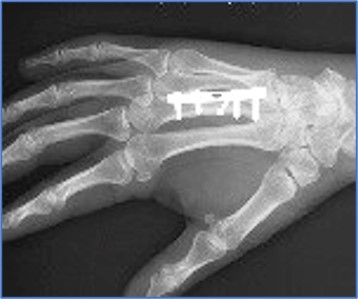

Finger Joint implants

Finger Joint Specification

ASTM F1781: Standard Specification for Elastomeric Flexible

Hinge Finger Total Joint Implants.

Finger Joint Wear Test

Customized test

Finger Implant Requirements

ISO 21534:Non-active Surgical Implants- Joint replacement

Implants- Particular Requirements.